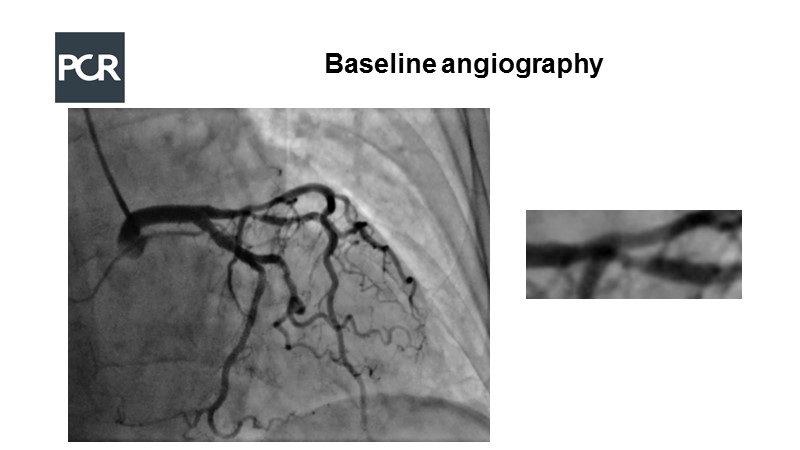

Watch this LIVE case to learn more on how to perform PCI of a long LAD-Diagonal bifurcation lesion using DK Crush technique.

A 71-year-old female presents with angina class 2. Coronary CT angiography shows multivessel disease and LAD-Diagonal bifurcation lesion can be seen on the angiogram…